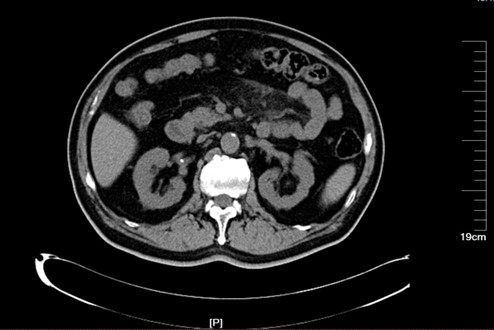

入院前腹部CT:

腹部CT示: 1.胸7-腰2椎体前外缘见流注样骨化,DISH待排; 2.腰椎退变,腰5/骶1椎间盘突出,骶椎椎板未融合; 3.肝囊肿;胆囊结石,肠系膜脂膜炎;4.双肾周渗出,双肾囊肿,部分复杂囊肿,双肾结石,慢性膀胱炎,膀胱小结石

前列腺钙化灶,动脉粥样硬化。